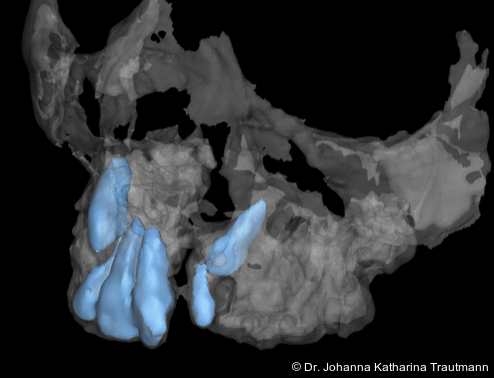

Zur genaueren Diagnostik der Lage beziehungen der Eckzähne und des Knochenangebotes im Spaltbereich kann neben den kieferorthopädi schen diagnostischen Unterlagen laut der S2 kLeitlinie Dentale digitale Volumentomografie6 auf eine dreidimensionale Bild gebung zurückgegriffen werden. In dieser zeigte sich eine vestibuläre Verlagerung des 13, eine palatinale Verlagerung des 23, sowie ein deutliches Knochendefizit im Spaltbereich mesial des hypoplastischen 22 (Abb. 2). Nach Auswertung der 3D-Daten erschien aufgrund der palatinalen Lage des 23 eine invasive Operation wie eine sekundäre Osteoplastik keinen entscheidenden Vorteil für die weitere Be handlung zu haben. In Rücksprache mit der Mund-Kiefer-Gesichtschirurgie der UMG wurde daher auf die OP verzichtet und initial die kieferorthopädische Therapie in den Vordergrund gestellt.